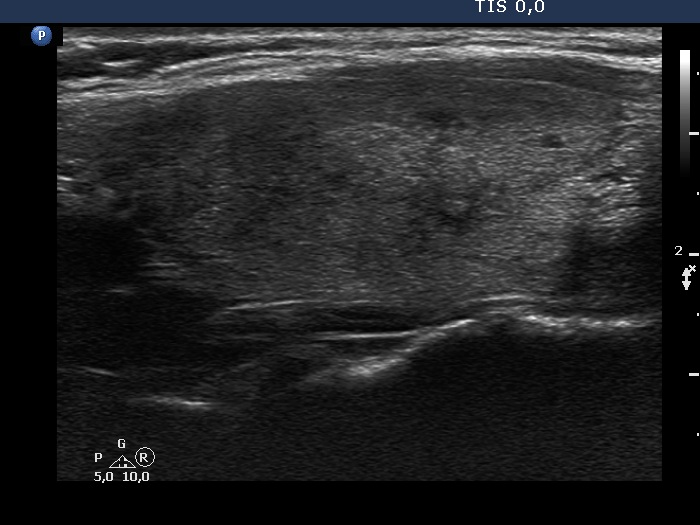

Initial examination (first row of images):

Clinical presentation: A 33-year-old woman was referred for evaluation of complaints suggesting hypothyroidism, including 12 kg weight gain, fatigue.

Palpation: Both lobes were palpable and not firm.

Laboratory examination: TSH 0.79 mIU/L, anti-TPO < 28 IU/mL.

Ultrasonography: The thyroid was echonormal and intact.